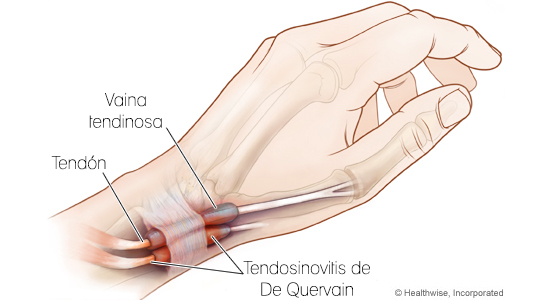

La Tenosinovitis de DeQuervain

Este trastorno se caracteriza por dolor e hinchazón en la muñeca y el área pulgar al agarrar, pellizcar, torcer, etc. Las posibles causas incluyen la inflamación vaina sinovial, el engrosamiento de los tendones en la base del pulgar, y los traumatismos repetidos o movimientos giratorios de la mano / muñeca.